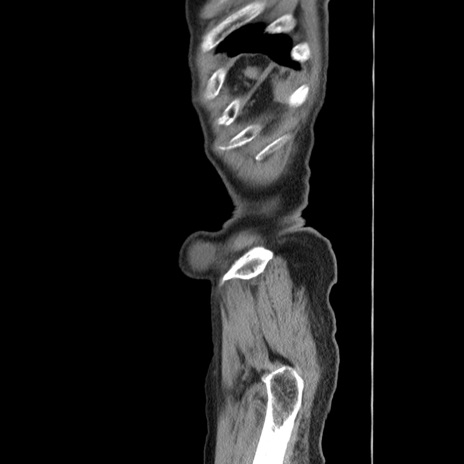

横断像